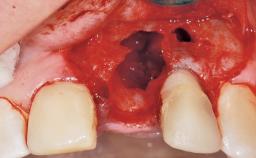

A 30-year-old female patient had lost tooth 21 and was referred to our clinic for consultation and treatment. Due to advanced apical infection, tooth 21 had been extracted two months earlier at another clinic and an acrylic-resin tooth had been bonded to the adjacent teeth. The patient desired implant treatment to avoid any damage to the adjacent natural teeth. While the patient had no history of any systemic disorder, she was a heavy smoker and exhibited medium to advanced periodontitis in the entire jaw. After the initial treatment to achieve a pocket probing depth of less than 4 mm and no bleeding on probing, a decrease in the height of the papillae mesial and distal to the extraction site and overall gingival recession were observed.

Bone Augmentation Horizontal|Staged

Augmentation Materials Autogenous chips|Membrane

Soft Tissue Anatomy Intact Defective

Bone Volume Horizontally and vertically sufficient Horizontally deficient Deficient vertically or deficient vertically AND horizontally

Bone Volume Deficient horizontally, requiring prior grafting